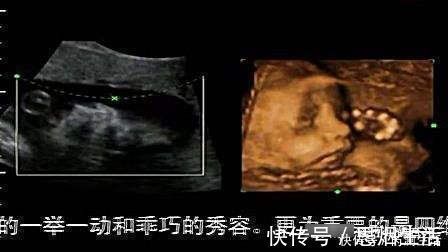

四维彩超不再是仅仅感觉宝宝的呼吸和运动,而是可以亲眼目睹他们的一举一动和乖巧的秀容。更为重要的是,四维彩超能够多方位、多角度地观察宫内胎儿的生长发育情况,为早期诊断胎儿先天性体表畸形和先天性心脏疾病提供准确的科学依据。